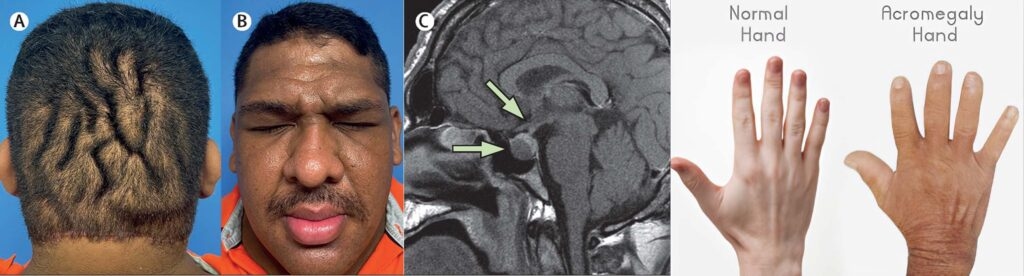

Acromegaly is an endocrine disorder that develops when the pituitary gland is hyperactive and produces excessive growth hormone. This results in increased bone size and height; a condition termed gigantism. However, if it occurs in adulthood, there is no change in height. Instead, facial features, hands and feet appear bigger. This condition is known as acromegaly.

Acromegaly has been associated with pituitary adenoma, a pituitary gland tumour. This tumour induces excessive production of growth hormone. This benign tumour grows slowly, and its effects may not be visible for many years.